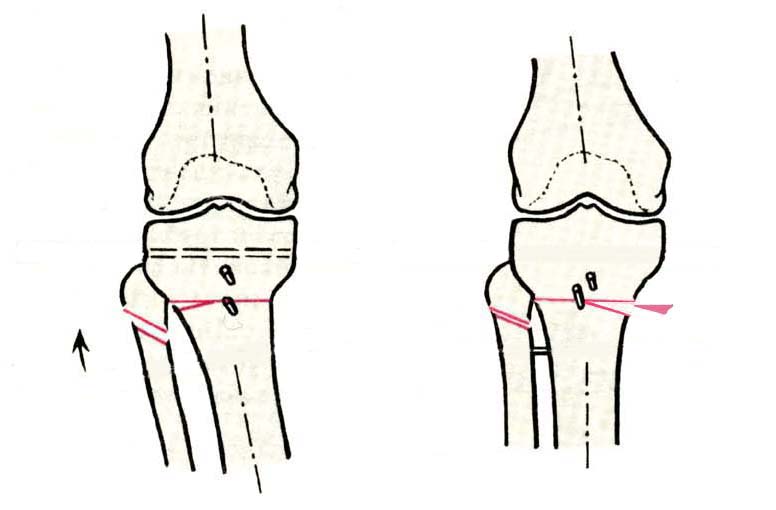

AC> Саша Артемьев, может, для данного случая свой вариант нарисуешь?

Из приведнной схемы не совсеим понял что означают разноцветные линии.

И зачем латерализация периферического фрагмента. Я всегда делаю медиализацию. См схему. И для данного случая медиализация подходит как нельзя лучше.

a> Я всегда делаю медиализацию. См схему. И для данного случая

Медиализация - это чисто эстетический прием, как я понимаю. Поскольку если делать остеотомию ниже вершины деформации, для восстановления оси надо делать смещение по ширине, в данном случае как раз латерализацию.

AC>>> Стоит ли медиализировать дистальный фрагмент?

AVM>> А зачем?

Красива...

Это значительно улучшает эстетический эффект, придавая полноту ногам.

Мне лично нравится:)

Технически при отсутствии опыта может показаться немного сложным. При навыке занимает минут 10.

И при этом не выходит за пределы нормальной оси.

Картинки - в приложении.Будут вопросы - готов ответить.

Ещё картинка - схема. Хотя у Соломина всё написано.